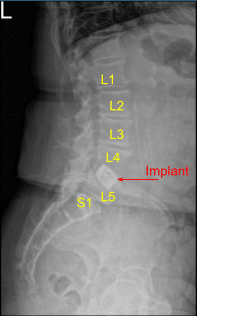

Given the concern for the implant in the prone position and our feeling that the endplates may have fractured more, we exposed the transverse processes for L4 and L5 and used the drill to create pilot holes in the pedicle on the left side at L4 and L5. Under fluoroscopy, we guided probes through the pedicles and tapped each pedicle, then placed pedicle screws into L4 and L5.

These screws were stimulated, and checked under fluoroscopy, and then a rode was placed and cap screws were given a final tightened. On the right side and left side, we decorticated the facets and transverse processes and placed our fusion mass for arthrodesis.